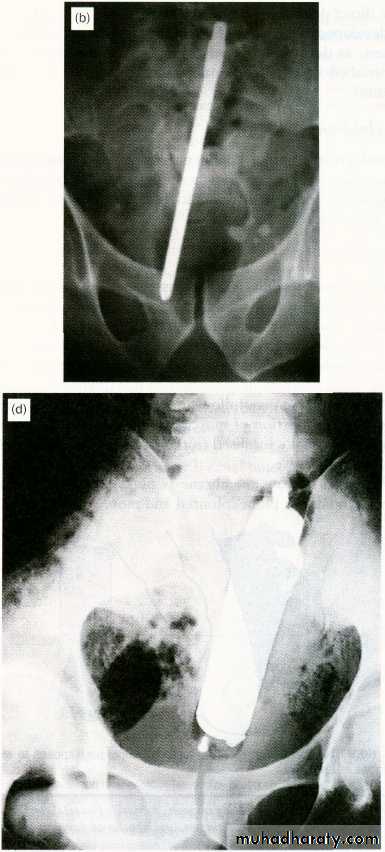

7-Insertion of a foreign body

Foreign bodies in the rectum

Treatment

- good clinical examination.- investigation such as proctoscope, sigmoidoscope if possible ,ultra-sound and ct-scan